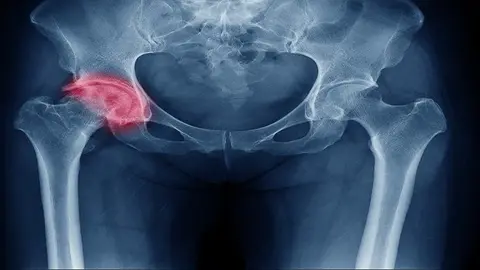

fractura de cadera

Radiografía de una fractura de cadera

Fractura de cadera, una lesión que afecta a 3 veces más mujeres que hombres